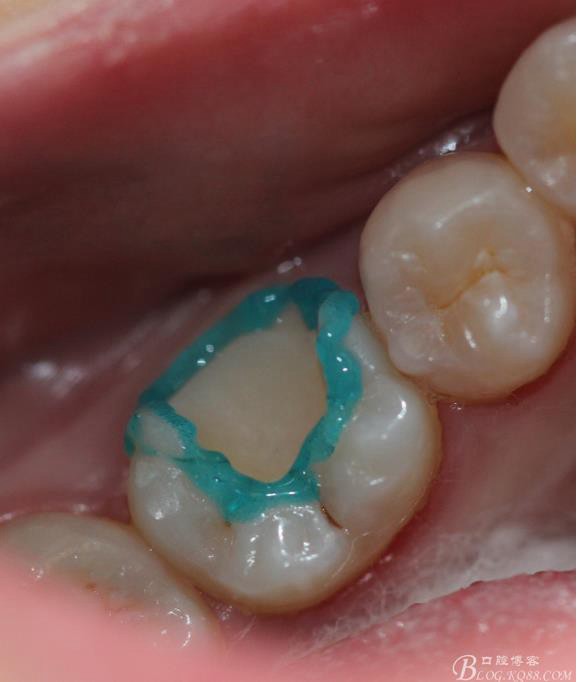

牙體隔濕酸蝕 牙釉質(zhì)15s 牙本質(zhì)20s進行濕粘接(不要吹太干)

粘接 去除多余的粘結(jié)劑 進行光照 調(diào)HE 一周后進行拋光